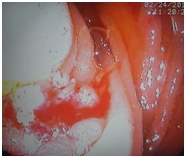

Колоноскопия

В области поперечной ободочной кишки определяется крупное стенозирующее циркулярное образование до 5 см, суживающее просвет кишки до 1 см, выражено контактно кровоточит, с трудом проходимо аппаратом. Выполнена биопсия на гистологическое исследование (с помощью струны-проводника для лучшего позиционирования аппарата).